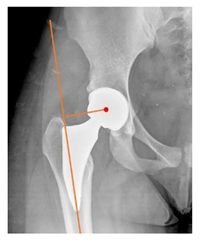

The mean follow-up was 6.6 ± 4.4 years (range 2–20). Two THR in two patients required revision. One patient with Albers–Schömberg disease required stem revision 33 months after the index procedure, due to stem undersizing and subsidence. Another patient with CDH sequelae underwent cup revision 68 months after the index procedure, because of recurrent hip instability due to initial vertical malposition of the cup. The overall survival rate of the cohort was 97.6% (95% CI: 84.9–99.7%) at 5 years of follow-up, 94.4% (95% CI: 79.8–98.6%) at 10 years and 15 years of follow-up (Figure 2). With the available data, Cox regression analysis could not detect any significant interaction between preoperative or intraoperative variables and the survivorship (p-value 0.242 to 0.989).

Postoperative radiographs showed a significant vertical malposition of the cup in 1 case (1.4%), a significant varus stem in 8 cases (10.8%) and a significant valgus stem in 1 case (1.4%). Two patients (2.7%) showed moderate heterotopic bone formation (Brooker ≥ 2), that did not significantly affect the hip motion and symptoms. All those THR that did not undergo revision showed good radiographic osteointegration, with no evidence of implant breakage, radiographic lucencies, bone defects, cup migration, or stem subsidence at the most recent radiographs.

In our experience, implant malposition was the only reason for implant revision. In one case, progressive subsidence was observed in a varus undersized stem, implanted in a boy with Albers–Schömberg disease; in another case, an excessively vertical cup with a 28 mm femoral head caused hip instability and required cup revision.

THR can be a challenging procedure in very young people. The combination of distorted anatomy, small physique, and poor bone stock can impede proper implant placement. Implant sizing may be an issue in these patients. The combination of young age and peculiar conditions such as skeletal dysplasia may require particular attention in preoperative planning and implant selection. Noticeably, we used the smallest size of the cup in 11 hips (15%) and the smallest size of the stem in 14 hips (19%). A meticulous preoperative planning, even using simulation software, [40,41,42] and careful implant selection, sometimes requiring even customized implants [37], is crucial in such conditions, to prevent unpleasant pitfalls during the operation.